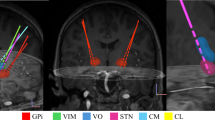

Once the simulations and modeling were performed, patients participated in two electrophysiology recording sessions. Figure 3A shows that the bilateral GPi-DBS lead locations for all patients (n = 10). During the two electrophysiology sessions, none of the patients reported any discomfort or complications. Furthermore, neurological assessments showed no change in their physical and mental condition before and after TUS applications.

A The localizations of the DBS leads in the GPi (n = 9 PD patients, n = 1 dystonia patient) demonstrated in both axial and coronal brain views. B Comparison of baseline spectral power across the tbTUS, 10 Hz TUS, active sham, and passive sham conditions, indicating no significant differences in total baseline LFP power spectra (3–30 Hz) prior to the application of TUS (Wilcoxon signed-rank test). Shaded areas represent the standard error of the mean. C–F Histograms represent the total percentage change in spectral power (3–30 Hz) from baseline following each TUS protocol. The data has been pooled across all 18 hemispheres (n = 9 PD patients) and at four different time points post-TUS. While tbTUS (C), and 10 Hz TUS (D) significantly increased the overall power from baseline (tbTUS: p = 0.01, 10 Hz TUS: p = 7E-06), passive sham and active sham TUS (E, F) had no significant effects (passive sham: p = 0.06, active sham: p = 0.8). Statistical Significance was tested by a two-sided Wilcoxon signed-rank test with Bonferroni adjustment. Asterisks indicate statistical significance (*p < 0.05, ***p < 0.001) and the pink downward-pointing triangles indicate the mean of the distribution. The vertical dashed line at 0% denotes the baseline level for reference.